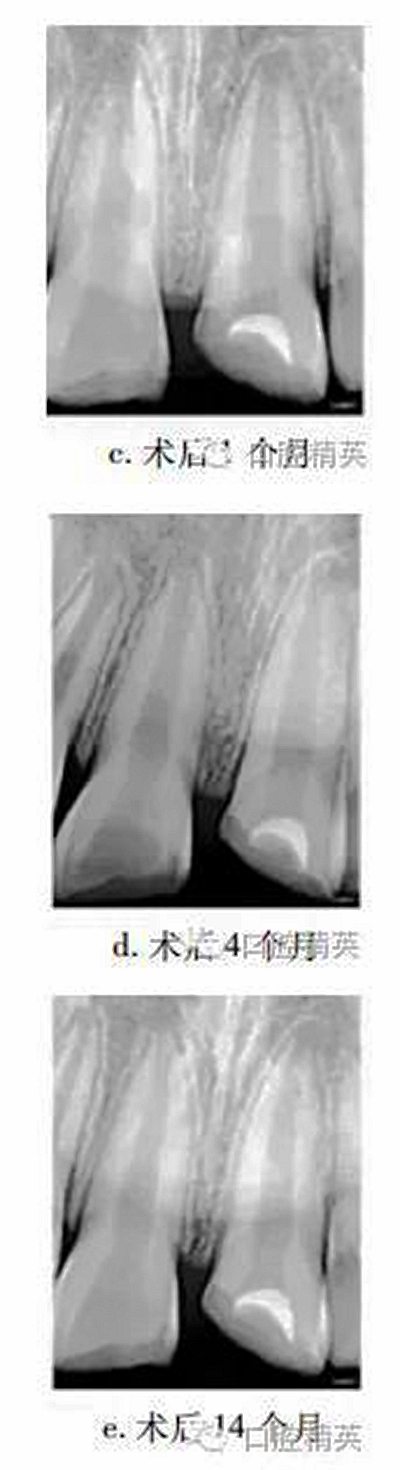

1個月后復(fù)查,21無明顯不適,上唇腫脹減輕,患牙冷熱診(-),牙髓電活力測試(-),X線片示根尖無明顯變化(圖c)。4個月后復(fù)查,患牙無明顯不適,冷熱診(±),牙髓活力測試(-),X線片示患牙根管腔略見縮窄(圖d)。14個月后復(fù)查,患牙無明顯不適,牙髓活力測試(+),但較正常對照牙低;X線片示:蓋髓劑下方可見斷斷續(xù)續(xù)的高密度影像,根管壁增厚,管腔明顯縮窄,根尖孔聚攏傾向,牙根長度較初診時增加(圖e)?;佳涝涮钗锫杂腥睋p,稍加預(yù)備后玻璃離子暫時恢復(fù)牙冠形態(tài)。

26個月后復(fù)查,患牙無不適,牙髓活力測試較正常牙齒略低,冠部充填物部分脫落,X線片示:患牙蓋髓劑下方可見連續(xù)薄層高密度影像,髓腔縮窄,根尖孔聚攏,牙根長度較鄰牙無明顯差異(圖f)?;佳廊コ糠植Aщx子水門汀,備釘?shù)?,隔濕,納米樹脂修復(fù)冠缺損,調(diào)牙合拋光。

眾多臨床研究表明,MTA用于活髓切斷術(shù)的臨床療效優(yōu)于傳統(tǒng)的蓋髓劑氫氧化鈣,除去MTA較氫氧化鈣具有更好的封閉性以外,低細(xì)胞毒性是其另一重要特點(diǎn)。MTA體外實驗中可促進(jìn)正常牙髓細(xì)胞的牙向分化能力,亦能提高成骨細(xì)胞的體外骨向分化能力。有學(xué)者發(fā)現(xiàn)早期炎癥狀態(tài)下,牙髓干細(xì)胞的體外增殖與成牙能力降低,而成骨能力上調(diào),本病例26個月復(fù)查X線片中發(fā)現(xiàn)MTA下方有薄層連續(xù)高密度影像,牙根伸長,根尖孔聚攏,提示創(chuàng)傷暴露后的牙髓(干)細(xì)胞在MTA誘導(dǎo)下,具有較強(qiáng)的修復(fù)能力。